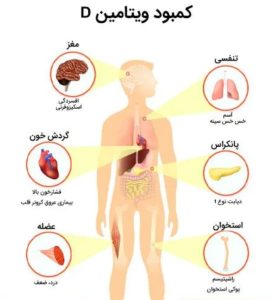

ویتامین D تنها برای سلامت استخوانها نیست؛ این ویتامین در سالهای اخیر بهعنوان یک تنظیمکننده مهم عملکرد عصبی، ایمنی و سمزدایی نورونی شناخته شده است. پژوهشهای گسترده نشان دادهاند که سطوح پایین ویتامین D میتواند مغز را در برابر سموم نوروتوکسیک مانند فلزات سنگین (سرب، جیوه) و ترکیبات آلی (حلالها، آفتکشها) آسیبپذیرتر کند. این مقاله خلاصهای از شواهد بالینی جدید درباره نقش کمبود ویتامین D در افزایش حساسیت به سموم عصبی مزمن را با نگاهی علمی و قابلفهم بررسی میکند.

ویتامین D در مغز بهشکل فعال کلسیتریول (۱,۲۵‑dihydroxyvitamin D₃) عمل کرده و در سراسر دستگاه عصبی گیرنده دارد، بهویژه در:

– هیپوکامپ و قشر پیشپیشانی (مراکز حافظه و تمرکز)

– مخچه و ساقه مغز (کنترل حرکتی و تعادل)

– تنظیم ترشح نوروترانسمیترها مانند دوپامین و سروتونین

– تعدیل کانالهای کلسیمی و گلوتامات برای جلوگیری از تحریک بیشازحد نورونی

– کاهش استرس اکسیداتیو و التهاب عصبی از طریق فعالسازی ژنهای دفاعی آنتیاکسیدان (Nrf2، GSH)

وقتی سطح ویتامین D زیر ۳۰ ng/mL سقوط کند، این محافظتها ضعیف شده و نورونها در برابر ترکیبات سمی آسیبپذیرتر میشوند.